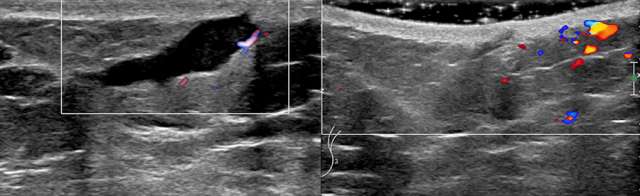

Ultrasound is the imaging modality of choice for solid masses as the superior spatial resolution allows for optimal definition of skin layers. On ultrasound, the dermal layer appears as a hyperechoic band overlying the relatively more hypoechoic subcutaneous fatty tissue. Lesions completely bordered within this echogenic dermal layer can be confidently considered dermal in origin. Dermal lesions can extend to the subcutaneous layer which may be difficult to distinguish from breast tissue origin. Sonographic features such as the “claw sign” and “tract-to-skin sign” are strongly suggestive of dermal origin (4). Another tool that improves spatial resolution of ultrasound is through the use of acoustic gel.